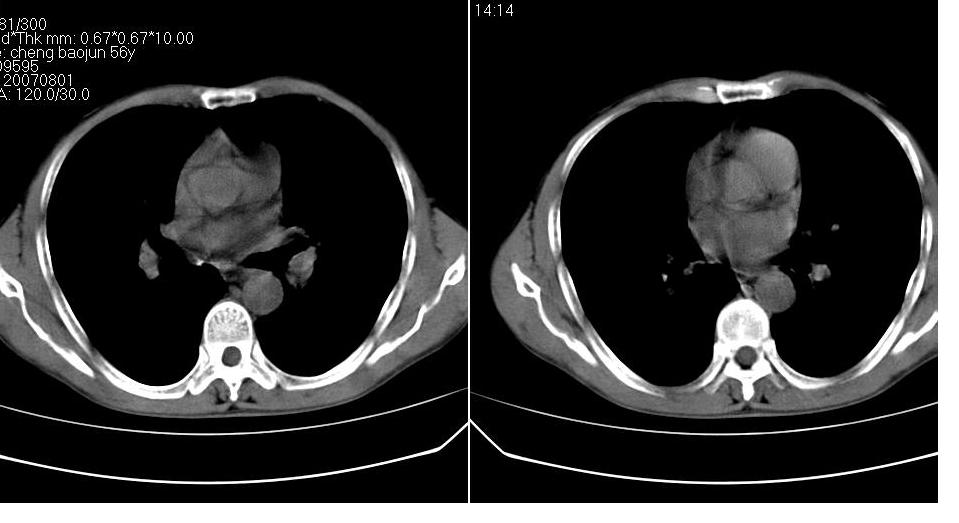

男 58岁 咳嗽,无明显不适.

右侧肺门肿块,右上叶不张,右上胸廓塌陷,气管纵隔右移,纵隔内有些小淋巴结,考虑中央型肺癌,作个支气管纤维镜取个病理吧,鳞癌的可能性大

右肺上叶中央型ca,右上叶支气管起始部变狭窄,致右肺不张,纵隔及腋窝淋巴结肿大,请结合纤维镜检查.

右侧肺门肿块,右上叶不张,右上胸廓塌陷,气管纵隔右移,纵隔内有些小淋巴结,考虑中央型肺癌伴右肺上叶不张,作个支气管纤维镜取个病理吧.